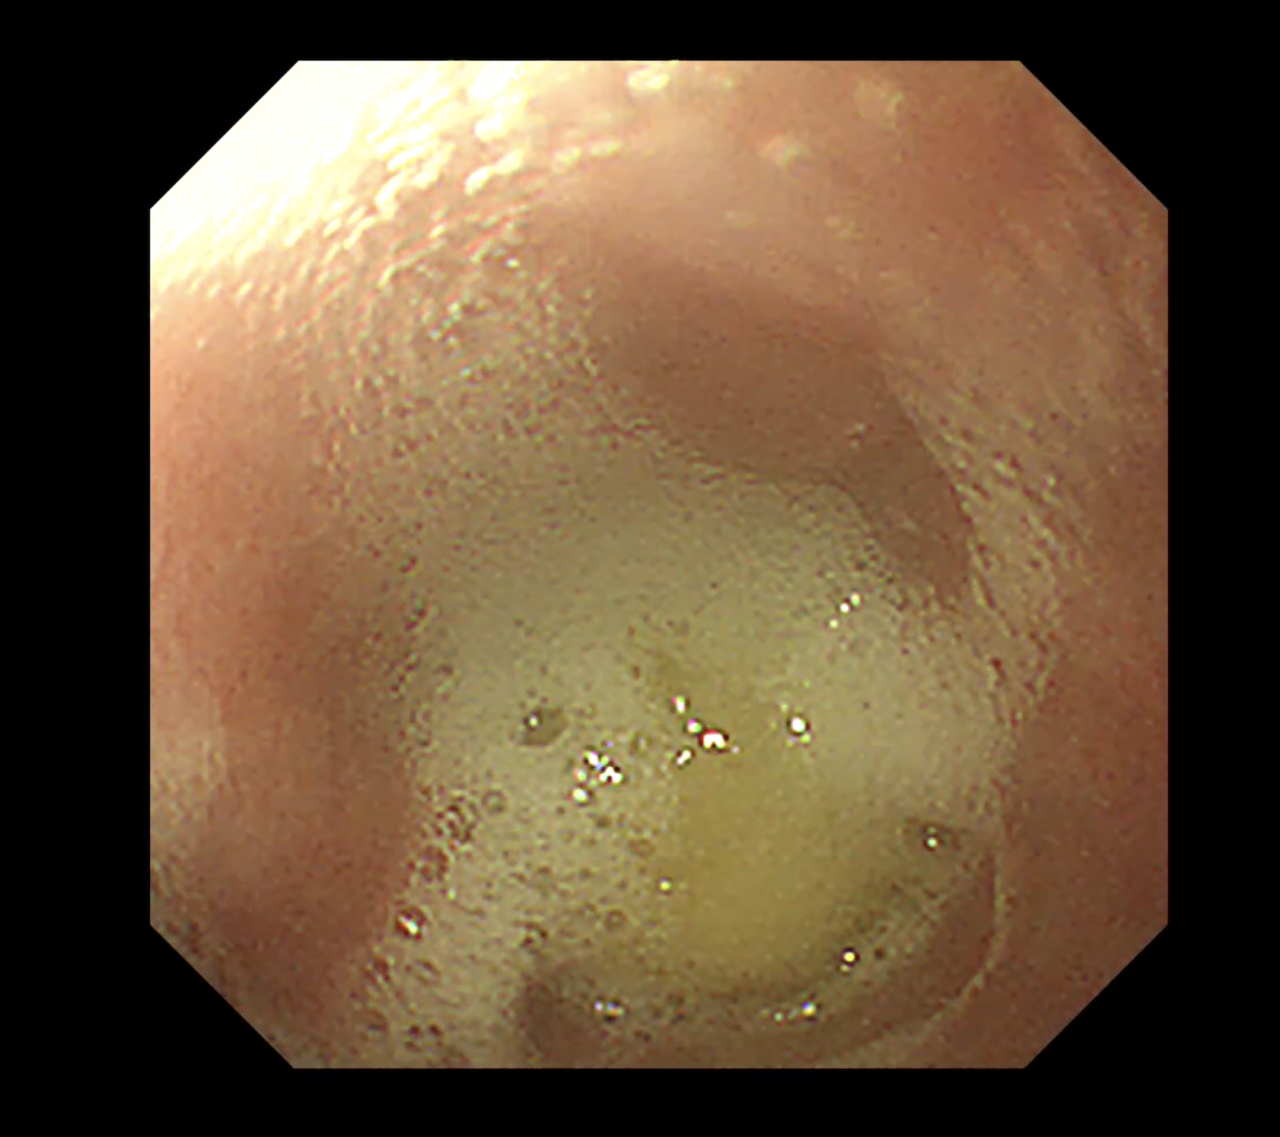

- 診断方法:X線および内視鏡検査

- 処置:内視鏡ガイドでストマックチューブを用いて慎重に胃内に落とし込む。